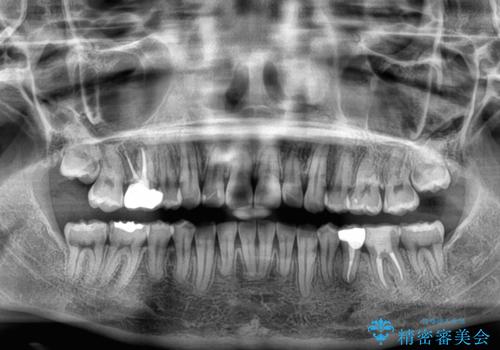

- 前歯のデコボコを気にして来院された患者様です。

上下の前歯にデコボコがあり、更にはディープバイトにより下顎前歯の大半が隠れている状態でした。

上顎左右第一小臼歯の2本を抜歯し、ワイヤー装置を使用して咬み合わせ高さを改善しながら、歯列を整えて行くこととしました。

事前にむし歯の疑いがある歯があり、処置を行いましたが、矯正治療中に失活してしまい、ワイヤー装置除去後に、根管治療とセラミッククラウンによる補綴治療を行いました。